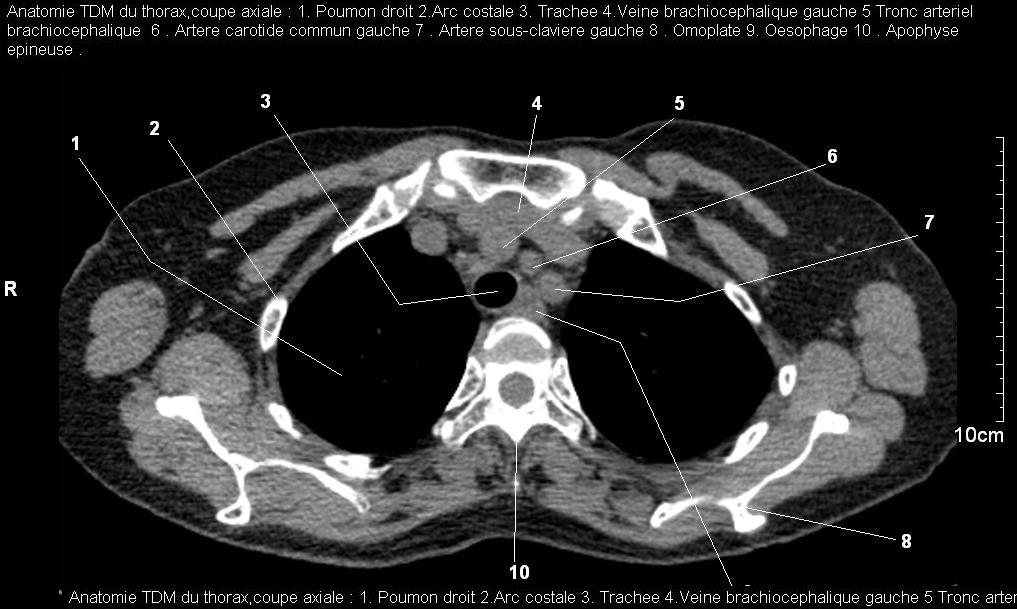

Radioanatomie pulmonaire ( image radiologie

thoracique normale )- La Tomodensitometrie du thorax (

coupes axiales fenetre mediastinale ) |

Les fenetres mediastinales permettre

d'etudier anatomie du mediastin , les structures vasculaires

en coupes axiales de 0,5-1cm sur le thorax . Ceux qui

s'installent travers le thorax de C4 a L1, L2

a n'a pas de contrast et se donnent des resutats

suivantes : |